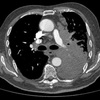

Homem, 60anos, dor torácica e abdominal de forte intensidade há 2 horas.

Dissecção de aorta abdominal, com artéria renal direita oriunda da luz falsa.